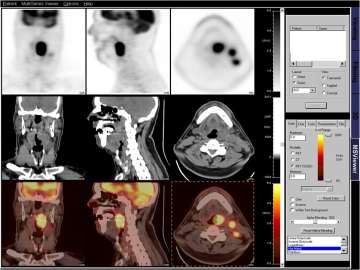

Figure 1: The images below represent different imaging modalities used by radiation oncologists to create a more personalized and informed treatment plan.

Head and Neck image showing a Biologically-guided Treatment Plan top - PET image, middle - CT image, bottom - PET/CT image